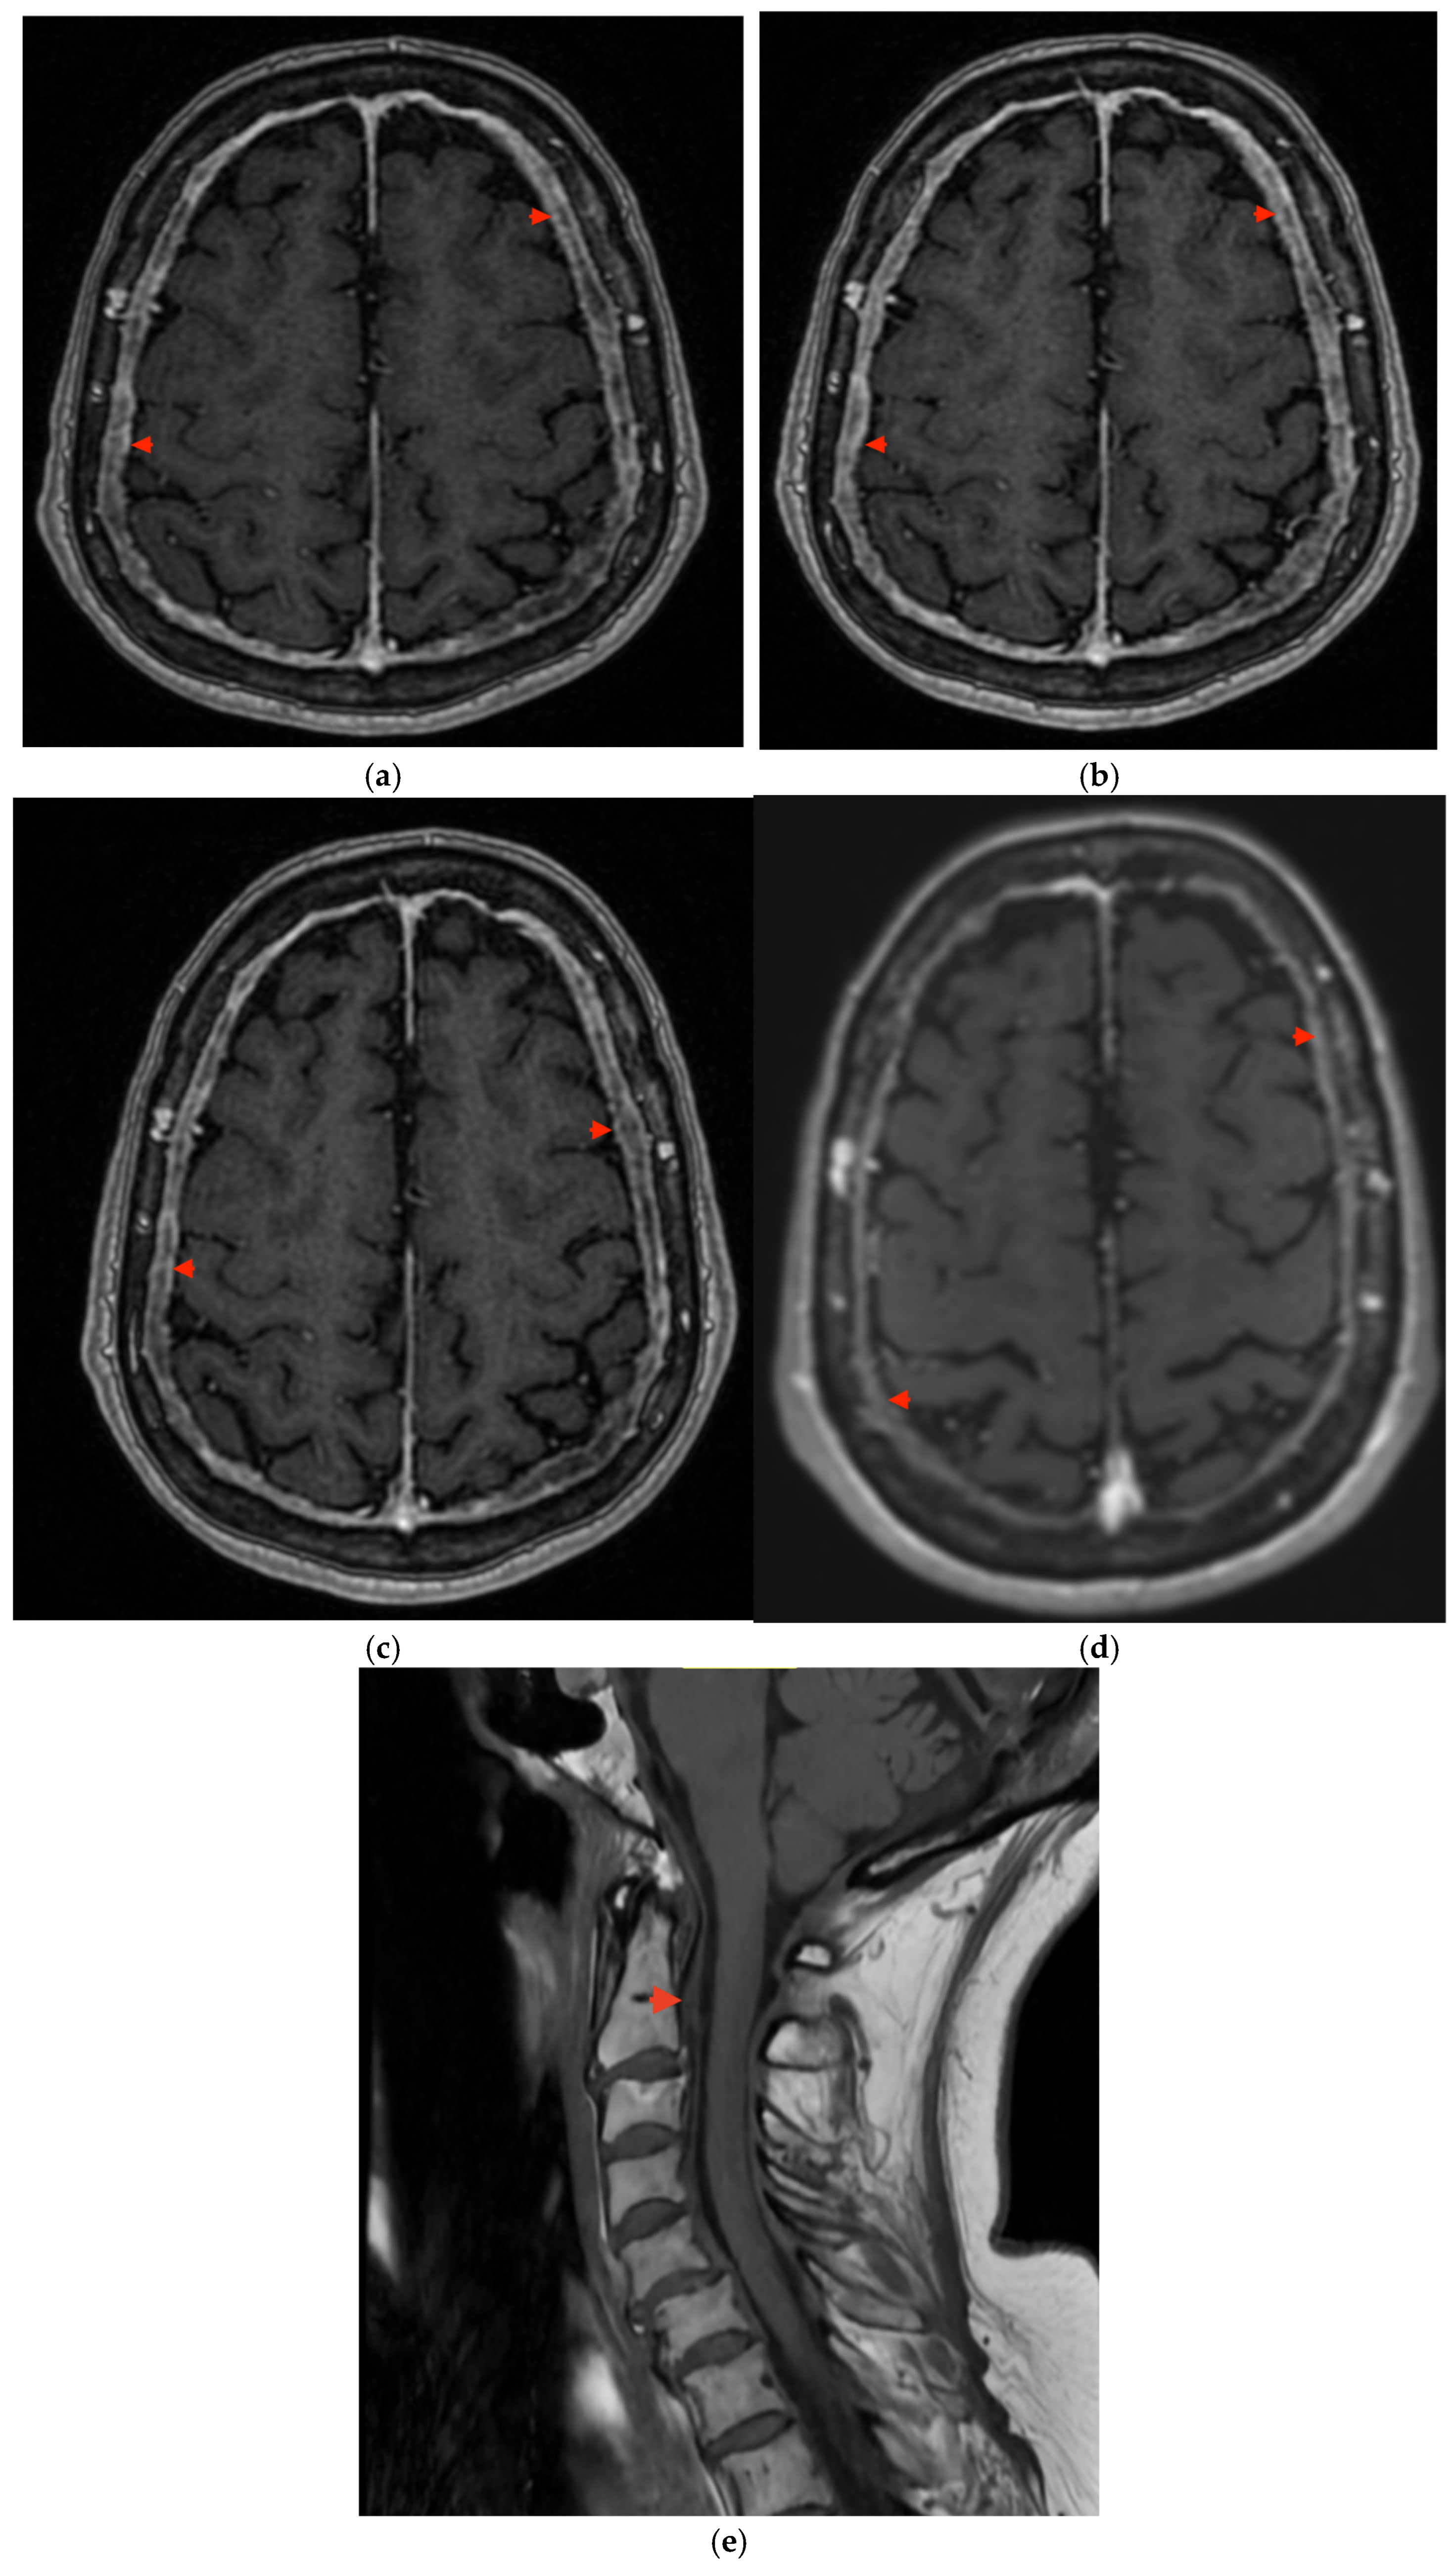

2. Case Presentation